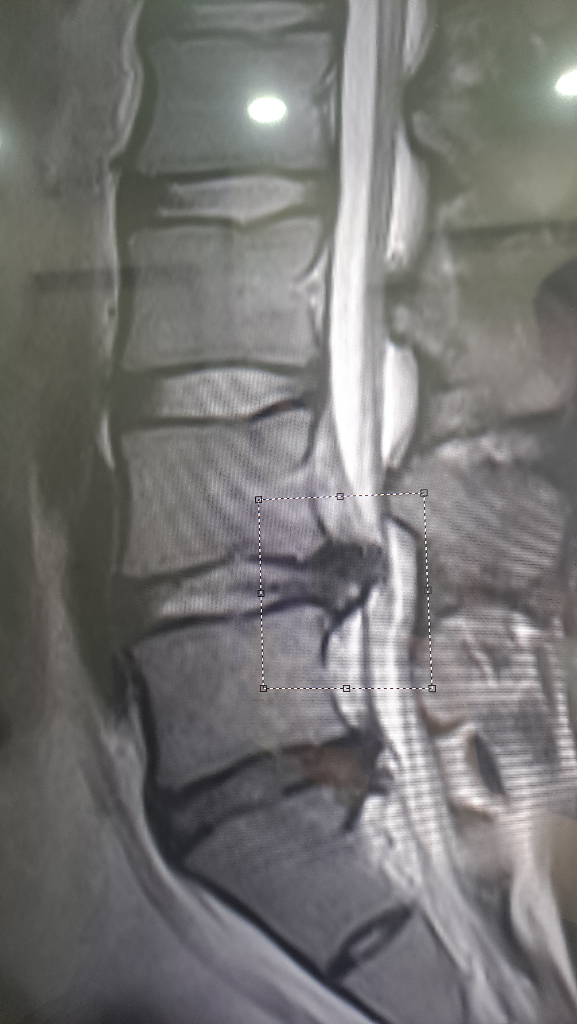

최근에 찍은 mri 결과인데 허리디스크가 심한 상태인가요?

척추전문 병원에 가서 mri를 찍으니 허리디스크라고 합니다. 척추전문병원 의사분께선 원래는 수술을 해야하는 상황인데 아직 제 나이가 젊기도하니 약물이나 시술을 먼저 해본뒤에 그때도 나아지지 않을시 수술을 하자고 하셨구요. 평소에 제가 다니던 동네의 정형외과 의사분께는 여쭤보니 엄청 심한건 아니니 주 1~2회 물리치료 받으면서 상태를 지켜보자 하셨습니다. 디스크가 터진지는 지금 약 10일정도 된거같습니다. 다음달에 대학병원 진료도 예약해놓긴 했는데 혹시 여러분들이 보시기엔 어떤거 같나요?? 보존치료로 충분히 치료가능할까요? 아니면 수술만이 답일까요?ㅠㅠ

• 1번 째 사진

보는 의사마다 소견에 차이가 있을 수 있습니다. 위 사진 두 장만 가지고 명확한 상태를 알 수 없지만 개인적으로 보았을 때에는 디스크가 상당히 많이 탈출하여 척수 신경이 상당히 많이 눌려 있어 심한 상태라고 볼 수 있어 보입니다. 다만 신경학적인 증상이 심하지 않다면 응급하게 수술을 해야한다고 보기는 어렵습니다.